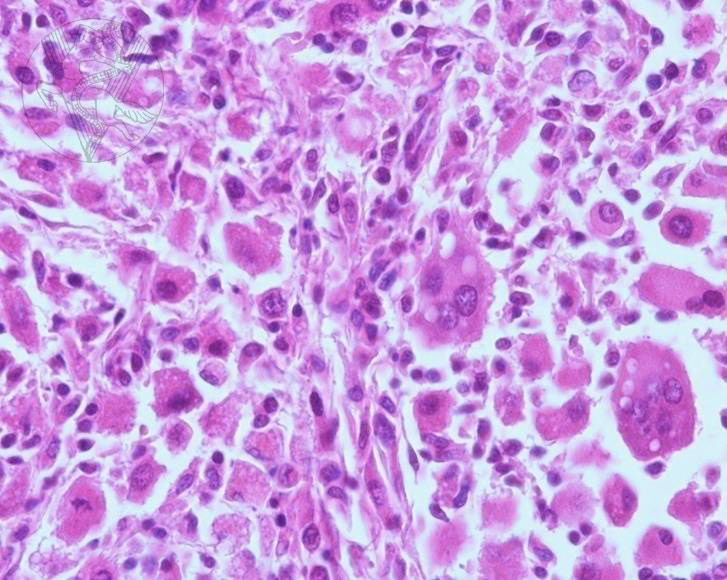

From www.researchgate.net

Photomicrograph of a soft tissue at an injection site in a dog Dog Soft Tissue Sarcoma soft tissue sarcomas (sts) arise from the neoplastic transformation of mesenchymal cells and comprise around 15 percent of all skin and subcutaneous. soft tissue sarcomas are very invasive into the surrounding normal tissue, and the tumor is usually larger than what is visible or palpable. the predicted outcome or life expectancy for dogs with soft tissue sarcomas. Dog Soft Tissue Sarcoma.